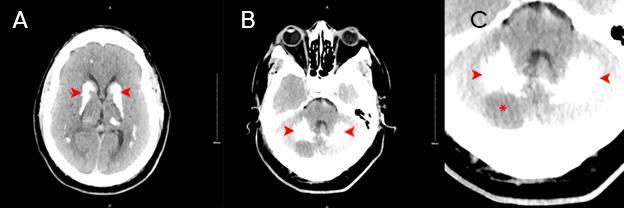

349 Acute Cerebellar Infarct in A Patient with Undiagnosed Fahr’s Syndrome: A Case Report

RW Slaven, M Huecker, D Kersting